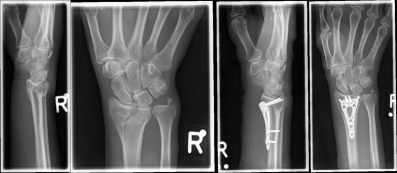

Pictures: A distal radius fracture with joint involvement (C-fracture) was treated with a plate osteosynthesis. After surgery, the plaster can be removed and physiotherapy exercises can be performed.